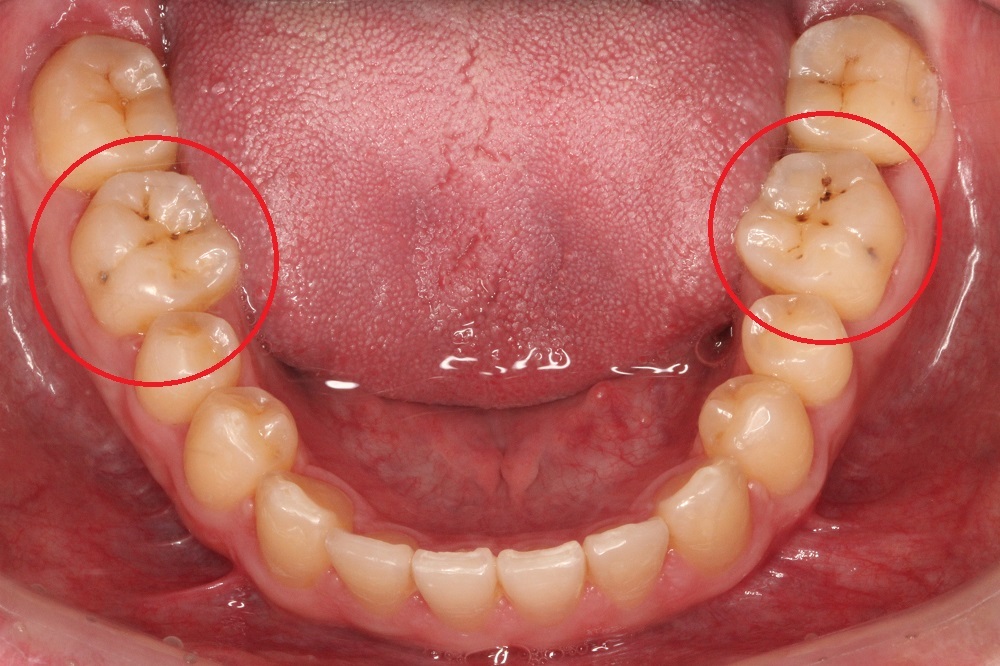

浅龋

破坏牙釉质,牙齿表面发黑有孔,一般没有明显的蛀牙洞,没有疼痛感。

治疗方法:树脂充填(补牙);采用正确的刷牙方式,养成良好的口腔卫生习惯,可以控制龋病发展。

中龋

病变进展到牙本质,有明显蛀牙洞,受外界的冷、热、酸、甜等刺激会出现疼痛反应,当刺激源去除后疼痛立即消失。

治疗方法:树脂充填(补牙)